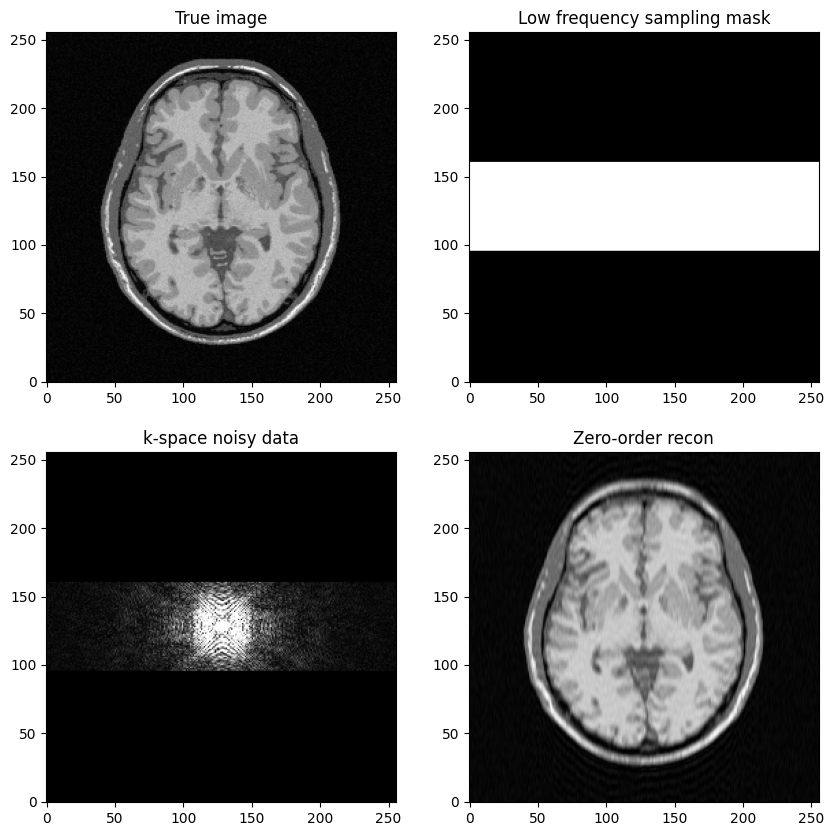

a low-frequency Cartesian mask is defined by the central lines of k-space.

To get started, the objective is to build a low-frequency sampling mask that consists of the central k-space lines

Fourier transform the reference MR image to compute k-space data, add zero-mean Gaussian complex-valued noise

Mask the data using the above defined mask

Next, perform zero-filled MR image reconstruction from masked k-space data

Study the impact of the number of lines in the mask on the final image quality

fig, axs = plt.subplots(2, 2, figsize=(10, 10))

axs[0, 0].imshow(mri_img)

axs[0, 0].set_title("True image")

axs[0, 1].imshow(kspace_masklines)

axs[0, 1].set_title("Low frequency sampling mask")

axs[1, 0].imshow(np.abs(kspace_data), vmax=0.01*np.abs(kspace_data).max())

axs[1, 0].set_title("k-space noisy data")

axs[1, 1].imshow(np.abs(image_rec0))

axs[1, 1].set_title("Zero-order recon")

plt.show()